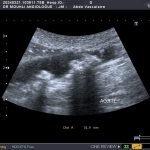

Il s’agit du cas typique d’une patiente présentant une sténose de l’aorte abdominale sous-rénale (sténose de l’aorte basse) à extension iliaque, découverte à l’occasion de la persistance de douleurs dorsales à irradiation fessière.

écho-Doppler artériel

Le diagnostic des thromboses aortiques présente une complexité notable, nécessitant une approche méthodique et l’utilisation de technologies d’imagerie avancées. Les thromboses aortiques, qui consistent en la formation de caillots sanguins dans l’aorte, peuvent entraîner des complications graves si elles ne sont pas identifiées et traitées rapidement. Les techniques diagnostiques les plus couramment employées incluent l’écho-doppler artériel et le scanner thoraco-abdominal injecté, chacune offrant des avantages uniques pour la détection des anomalies vasculaires.

L’écho-doppler artériel est souvent la première étape dans l’évaluation des thromboses aortiques. Cette technique utilise des ultrasons pour visualiser le flux sanguin et détecter toute obstruction ou anomalie dans l’aorte. L’écho-doppler permet non seulement de confirmer la présence d’une thrombose mais aussi d’évaluer sa taille et son emplacement précis. Toutefois, cette méthode peut être limitée par la qualité de l’image obtenue, surtout chez les patients ayant une anatomie complexe ou de l’athérosclérose avancée.